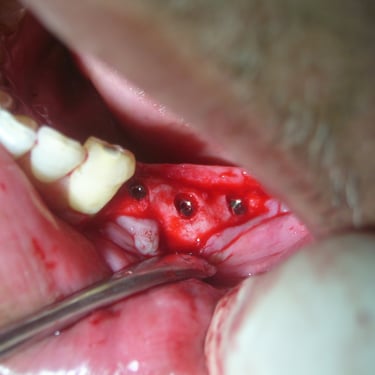

Oral and Maxillofacial Surgery

Extractions Frenectomy Flap surgery and bone grafting Wisdom teeth removal Surgical extractions Bone curettage Pericoronal flap removal